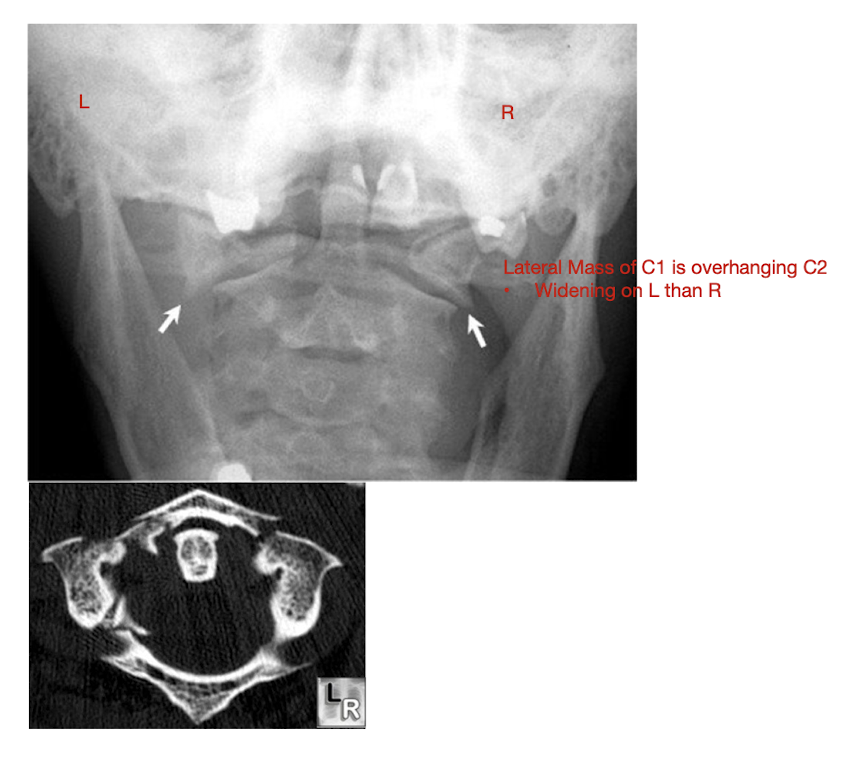

Upper C/S Fx

Fracture of C1: Jefferson Fx

What type of Fx is a Jefferson Fx?

AKA:

MOI:

Structures affected:

Compression Fx

MOI:

Hyper Ext or Flexion Injury of the Head

AKA:

Burst Fx

Structures affected:

Anterior and Posterior Arches of the Atlas

Fracture of C1: Jefferson Fx

Rarely causes ___ injury

What direction of neck movement can cause head to slide forwards and compress SC?

Requires what type of view to diagnose?

Note displacement of what structure?

Neurological Injury

Fwd flex w Jefferson Fx

Open mouth view

Lateral Mass Displacement